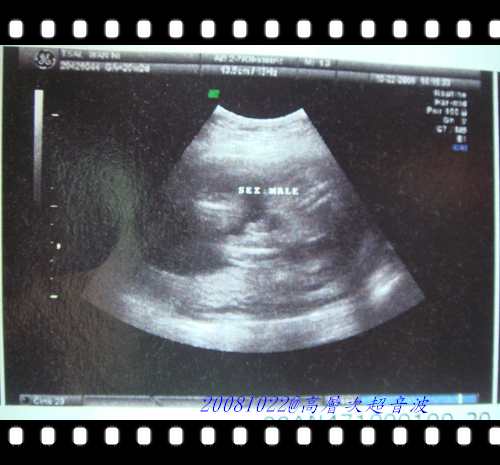

這張是寶寶的小弟弟喔!!呵呵....再次確認他是男生喔!!沒想到還沒出生的私密照就被我放上來摟 !!